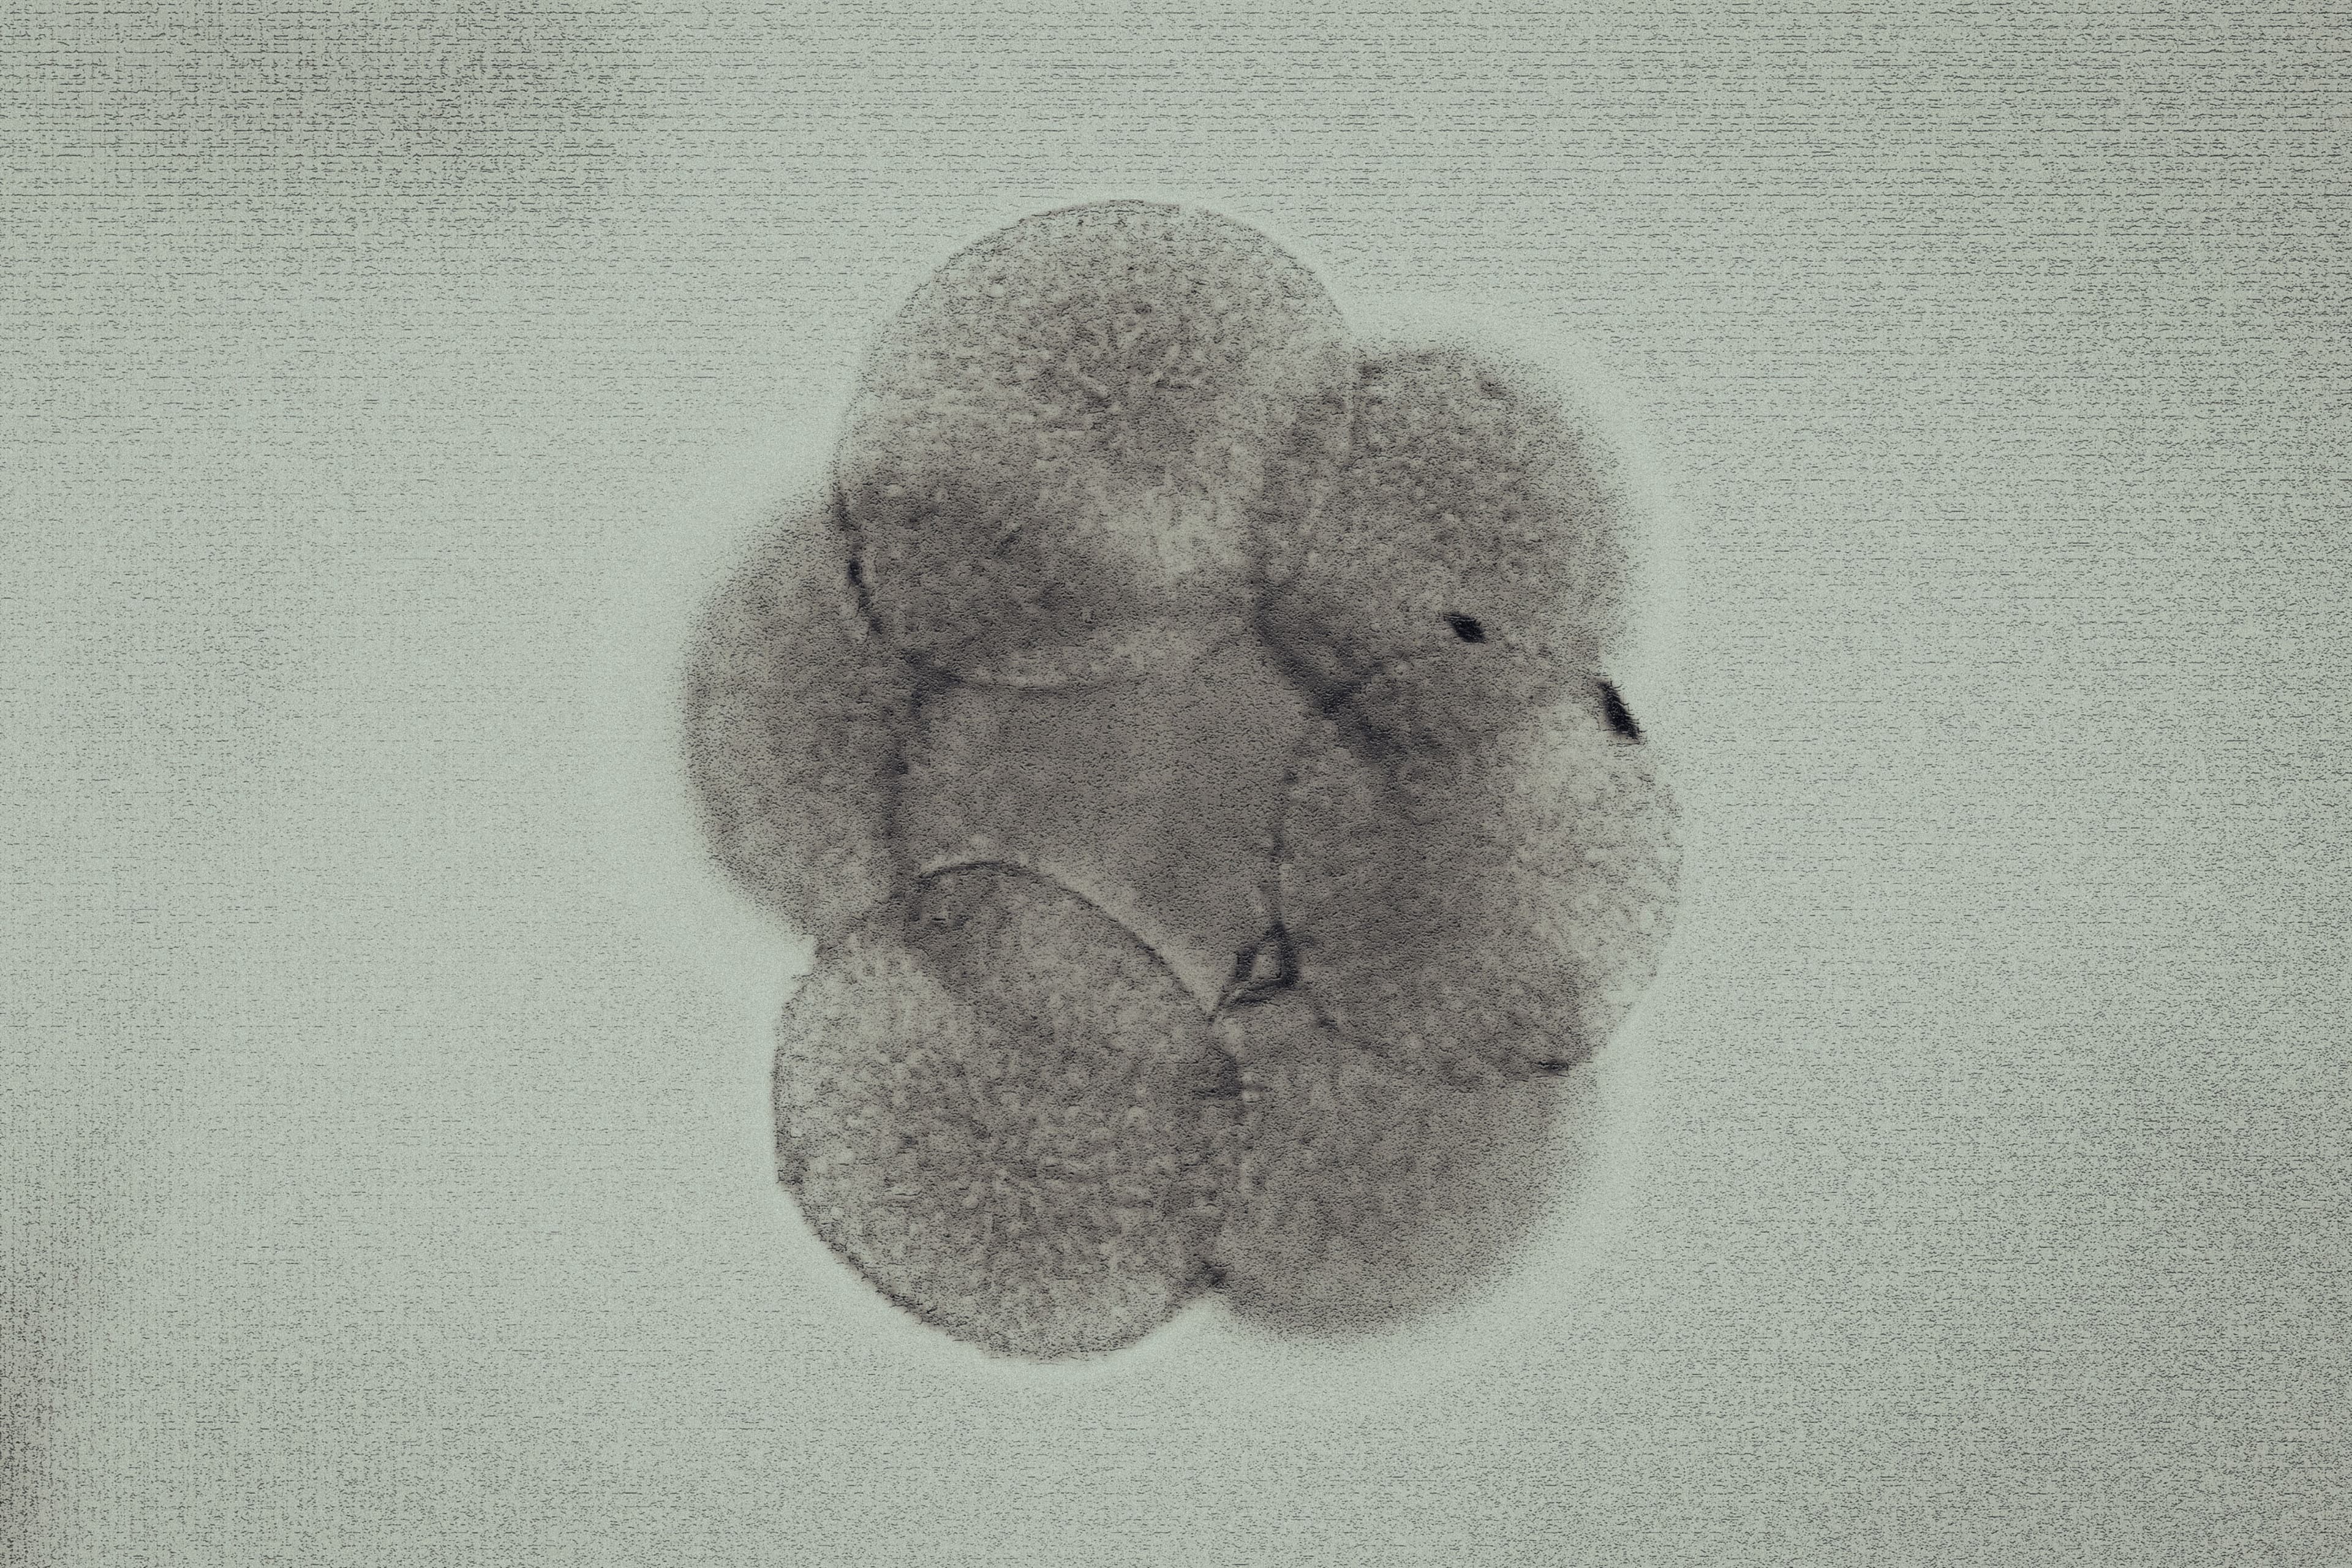

For decades, we’ve understood our increasing ability to genetically engineer our offspring through a sci-fi lens. Technology promised a future of pure human excellence — peak intelligence, strength and beauty without any defect, or so we heard in film and literature. From this, we derived a great fear of our own ingenuity; if we can design the best of humanity, what terrible fate awaits those who are less than perfect? Yet for all the fictionalized notions of eugenic horror, the science behind assisted reproduction technology (ART) such as in-vitro fertilization (IVF) may suggest a dysgenic future, one no less concerning than that portrayed by movies like Gattaca — and it could already be out of our control. Far from perfecting humanity, what if we’re IVFing ourselves out of existence?